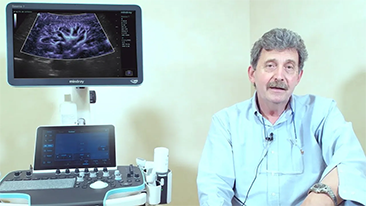

How Clearly Can You See a Liver?

Ultrasound contrast imaging plays a significant role in identifying focal liver lesions, such as hemangioma or liver cancer.

Ultra-wide non-linear UWN+ contrast imaging technology provides better penetration, higher contrast-tissue ratio, with lower MI and longer perfusion time observation.